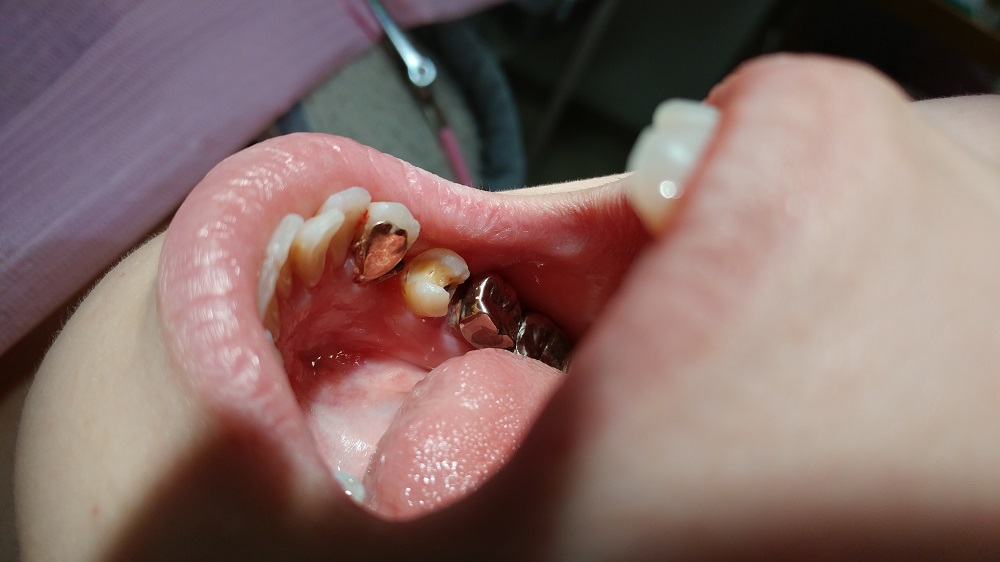

まず、奥歯の詰め物を全部除去して少し形を整える

また一つ手前の犬歯にはパーツを入れるための溝を掘る

ごく浅い、エナメル質に限定した溝の為に麻酔もしなくて良いのが利点だ

奥の歯に詰め物がなければ、ここも少しの溝を掘るだけになった事だろう 麻酔なしで

そして型をとる まずはそれだけである